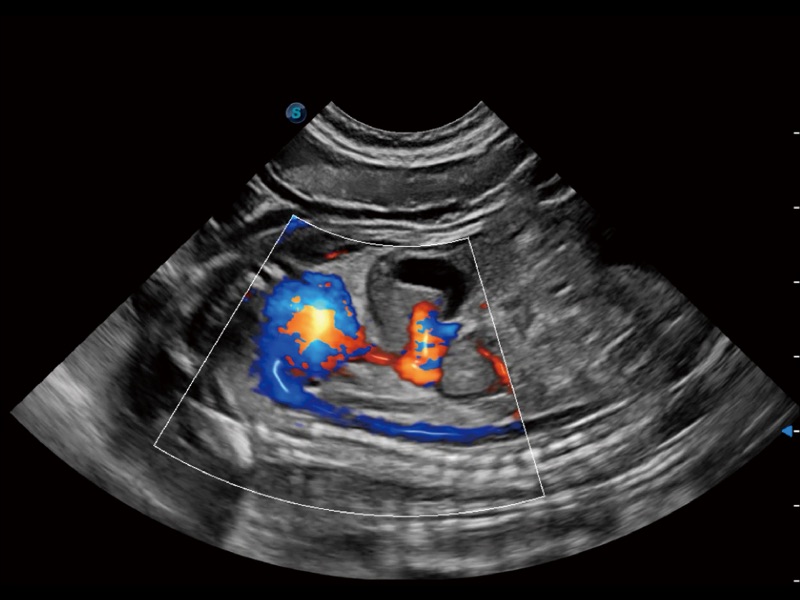

优异的基础图像

(犬)胎儿主动脉弓立体血流